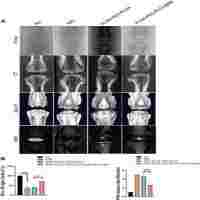

| Abstract | Degeneration of intervertebral discs (IVDs) results in an overall alteration of the biomechanics of the spinal column and becomes a major cause of low back pain. In this study, an injectable hydrogel composite is fabricated and characterized as a potential scaffold for the treatment of degenerated IVDs. Crosslinking of type II collagen-hyaluronic acid (HA) hydrogel with 1-ethyl-3(3-dimethyl aminopropyl) carbodiimide (EDC) increases the gel stability against collagenase digestion and reduces water uptake in comparison with non-crosslinked gel. Cell viability assay exhibits the proliferation of human nucleus pulposus (HNP) cells in hydrogels. The cells in non-crosslinked gel and the gel crosslinked with a low concentration of EDC (0.1 mM) show superior cell viability and morphology compared with cells in gels crosslinked with higher concentration of EDC. Quantitative PCR assay demonstrates the gene expression of extracellular matrix (ECM) by cells cultured in the gels. The expression of ECM genes by HNP cells in the gels demonstrated the phenotypic change of the cells. This study suggests that the type II collagen-HA hydrogel and crosslinked hydrogel (0.1 mM EDC) are permissive matrix for the growth of HNP cells and can be potentially applied in NP repair. |